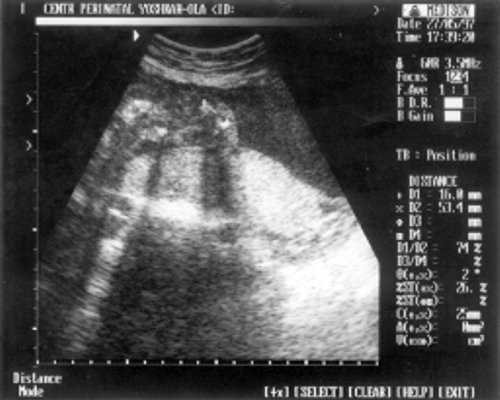

Плечевая кость = 16 мм - 14,5 нед. (рис. 3)

- Плечевая кость = 16 мм - 14,5 нед. (рис. 3)

Рис. 3. УЗИ плода - плечевая кость.